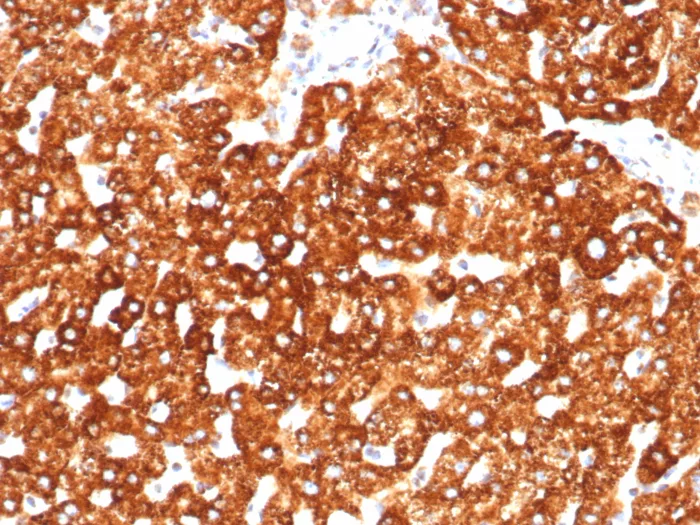

Immunohistochemistry-Paraffin: Haptoglobin Antibody (HP/3838) [NBP3-26805 ] -

Formalin-fixed, paraffin-embedded human liver stained with Haptoglobin Antibody (HP/3838). HIER: Tris/EDTA, pH9.0, 45min. 2°C: HRP-polymer, 30min. DAB, 5min.